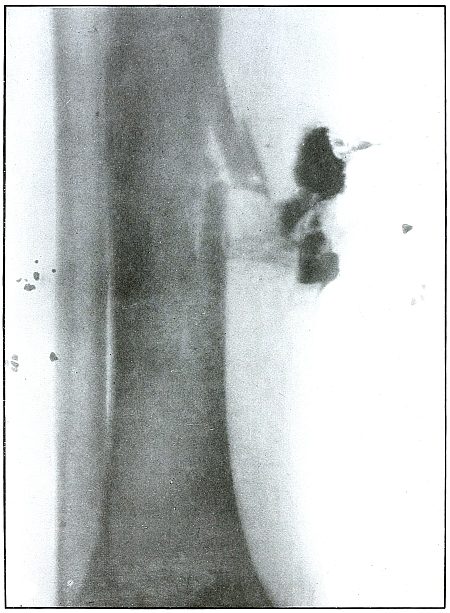

Plate 52.

[Pg 115]

Rifle—Plate 52.

LOWER EXTREMITY.

Gunshot Fracture of the Upper Shaft of the Femur.

The course of the bullet was anteroposterior and pierced the axis

of the shaft of the femur with three radiating lines of fracture,

resulting from the perforating action of the bullet striking the bone

at long range and with greatly reduced energy.

This plate shows the lateral separation of large fragments,

which is typical of gunshot wounds of long range.

Such wounds are usually not infected.

Emergency treatment is antiseptic dressing and coaptation with

extension and temporary splint, so that it may support the bone for

transportation and may be easily removable at place of continued

treatment.

In these cases with lateral separation of fragments, it is imperative

to supplement extension with pressure in a line perpendicular to the

long axis of the femur.